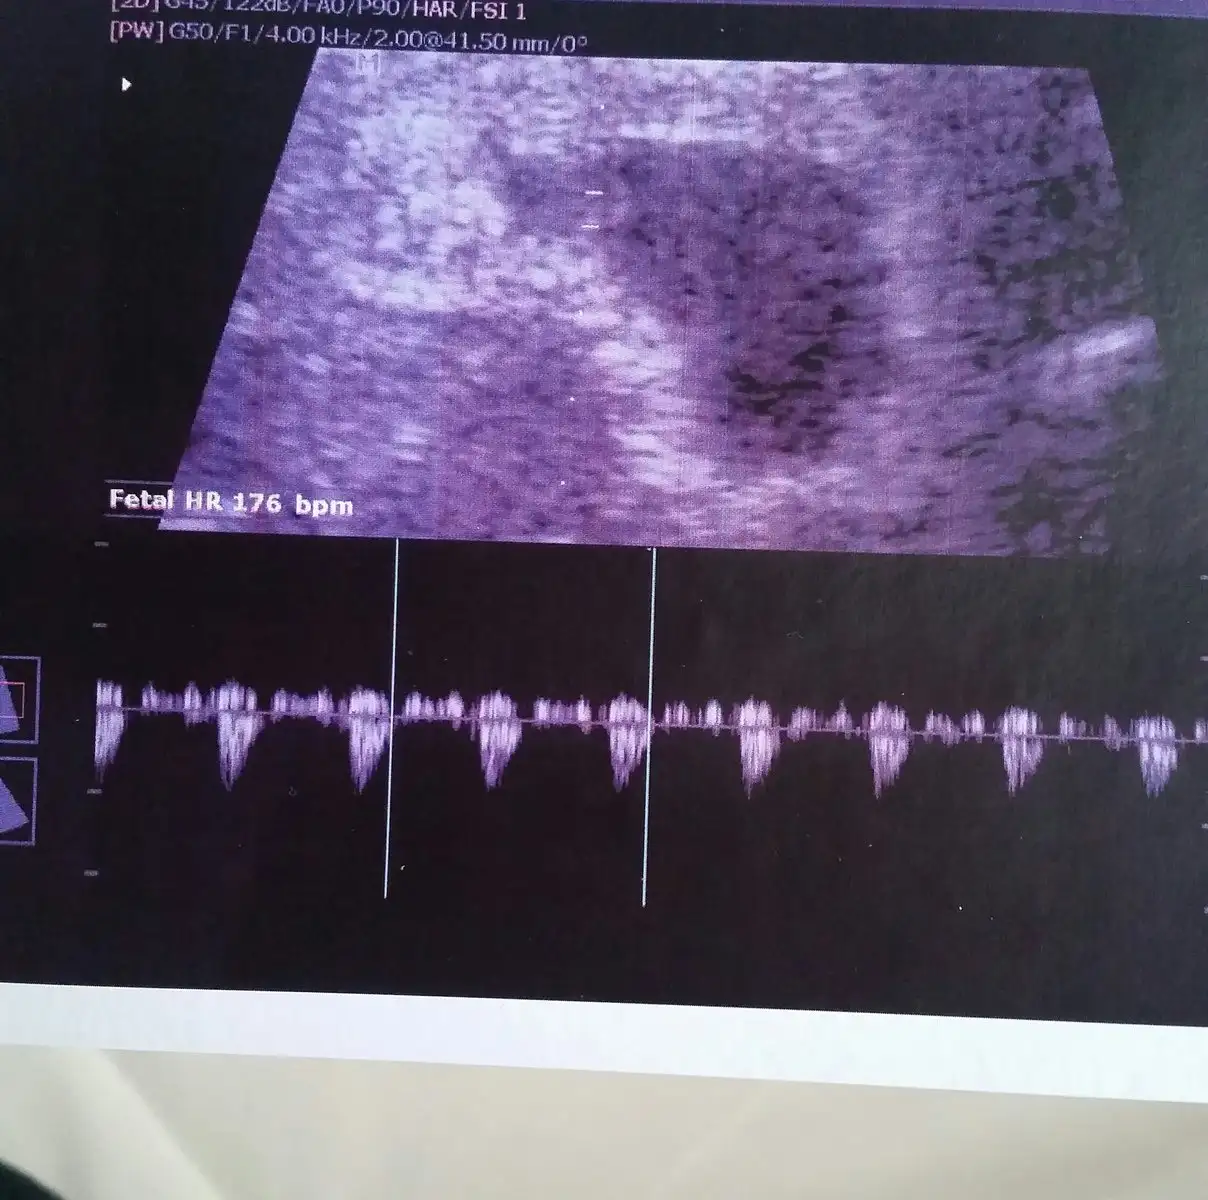

Canım sol atta yazıyo bak bizde, ben özellikle sordum zaten dakikada kaç atıyo kalbi diye, doktor 176 dedi. Ultrason kağıdı da böyle. Bana bi sorun olmadığı sürece artık 11-12.hafta gibi gel ama biliyorum sen dayanamazsın dedi, o zamana kadar bi kere daha gelebilirsin istiyosan dedi. Ben de 9.hafta da falan bi gidiyim diyorum dayanamam çünkü o kadar